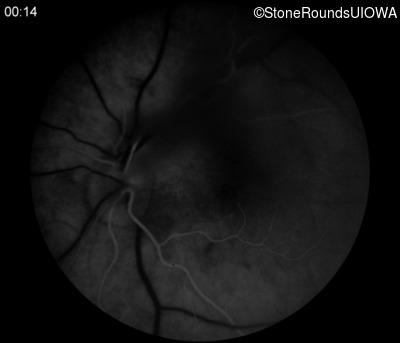

Fluorescein Angiography - Right - 20/50 -1 sc

Exemplar

Fluorescein Angiography - Left - 20/60 sc